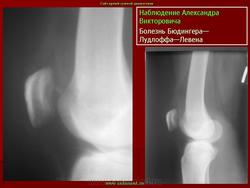

ХОНДРОПАТИЯ НАДКОЛЕННИКА (болезнь Левена). Этиология и патогенез. Чаще всего развивается после мелких повторных травм надколенника (у футболистов, бегунов, баскетболистов и т. д.), значительно реже — после однократной сильной травмы.